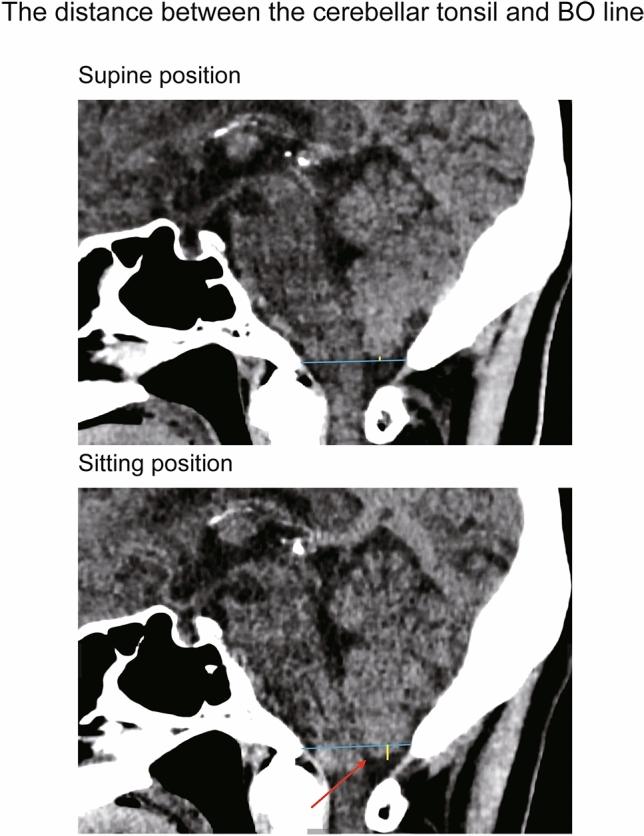

We aimed to use upright computed tomography (CT) to depict posture-related changes in the brain tissue under normal gravity. Thirty-two asymptomatic volunteers underwent upright CT in the sitting position and conventional CT in the supine position on the same day. We compared the shift of the pineal body, cerebellar tonsil, the length of pituitary stalk, optic nerve sheath area and perimeter (ONSA and ONSP, respectively), and lateral ventricular volume between the supine and sitting positions. We also compared shape changes of the cerebrospinal fluid (CSF) spaces at different sites between both positions. In the sitting position, the pineal body shifted 0.68 ± 0.27 mm in the ventral direction and 0.76 ± 0.24 mm in the caudal direction, the length of pituitary stalk decreased by 1.23 ± 0.71 mm, the cerebellar tonsil descended by 2.10 ± 0.86 mm, the right ONSA decreased by 15.21 ± 6.54%, the left ONSA decreased by 15.30 ± 7.37%, the right ONSP decreased by 8.52 ± 3.91%, the left ONSP decreased by 8.20 ± 4.38%, and the lateral ventricular volume decreased by 5.07 ± 3.24% (all P < 0.001). We also observed changes in the shape of CSF spaces with changes in posture. We concluded that the intracranial structure of healthy subjects and volume of ventricles changed according to posture on Earth.

我们旨在使用直立式计算机断层扫描(CT)来描绘在正常重力下脑组织与姿势相关的变化。32 名无症状志愿者在同一天分别接受了直立位 CT 和仰卧位 CT。我们比较了松果体、小脑扁桃体、垂体柄长度、视神经鞘面积和周长(分别为 ONSA 和 ONSP)以及侧脑室体积在仰卧位和直立位之间的变化。我们还比较了两种体位下不同部位脑脊液(CSF)空间的形状变化。在直立位时,松果体在腹侧方向上移动了 0.68±0.27mm,在尾侧方向上移动了 0.76±0.24mm,垂体柄缩短了 1.23±0.71mm,小脑扁桃体下降了 2.10±0.86mm,右侧 ONSA 减少了 15.21±6.54%,左侧 ONSA 减少了 15.30±7.37%,右侧 ONSP 减少了 8.52±3.91%,左侧 ONSP 减少了 8.20±4.38%,侧脑室体积减少了 5.07±3.24%(均 P<0.001)。我们还观察到 CSF 空间的形状随姿势的变化而变化。我们得出结论,健康受试者的颅内结构和脑室体积会根据地球的姿势而改变。